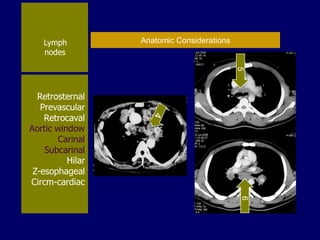

Lymph

nodes

Retrosternal

Prevascular

Retrocaval

Aortic window

Carinal

Subcarinal

Hilar

Z-esophageal

Circm-cardiac

Anatomic Considerations